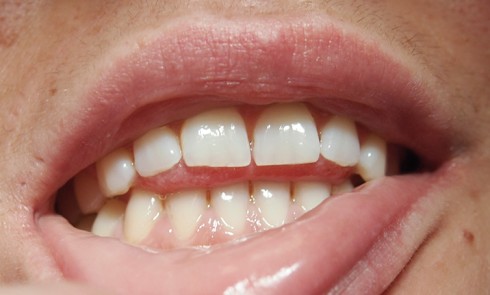

Une patiente consulte car elle ne supporte plus le port de sa prothèse amovible mandibulaire, pourtant suffisamment stable grâce à...